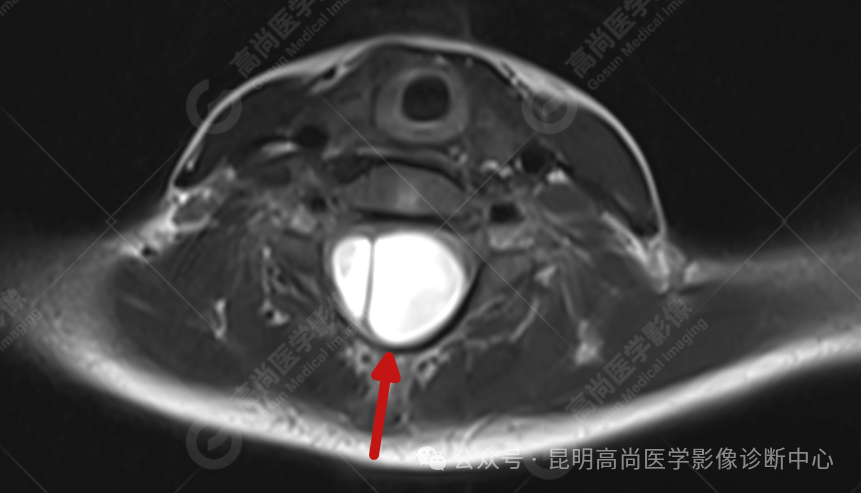

患者女,5 岁,出生时发现颈部包块,大小 3 cm×3 cm,5 年来无变化,拟行手术治疗,要求增强核磁协诊,否认体内金属物,无过敏史。

T2WI_tra

影像表现

颈 3-5 层面颈后部软组织不规则片状异常信号影,脊膜膨出可能;颈 3、4 棘突局部显示不清;颈胸髓内(约颈 3-胸 9 椎体水平)异常信号影,考虑囊肿并局部颈髓空洞可能,肿瘤或其他待排;请结合临床及相关检查。